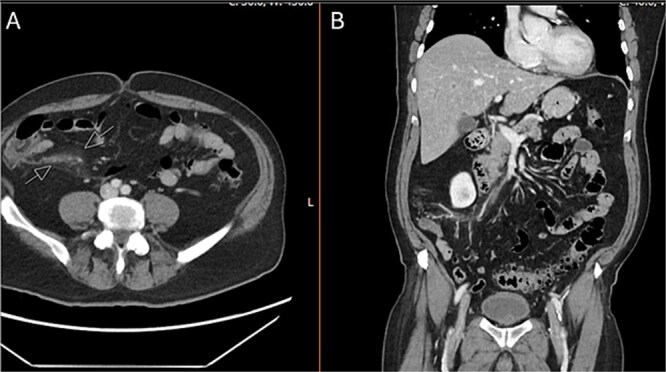

肠致病性大肠杆菌(EPEC)是大肠杆菌的一种致病性菌株。肠系膜静脉血栓性静脉炎是外科关注的问题,因为有肠缺血发展的风险。我们提出一个独特的情况下,病人与EPEC腹泻谁随后发展回肠结肠血栓性静脉炎。我们的病人以6天的腹泻和腹痛就诊于急诊科。腹部和骨盆计算机断层血管造影(CTA)显示回结肠静脉闭塞伴静脉周围炎症,符合肠系膜血栓性静脉炎。胃肠道聚合酶链反应(GI PCR)显示EPEC阳性。患者非手术治疗,静脉注射抗生素和抗凝治疗,症状消退。回结肠血栓性静脉炎是一种罕见的急性腹痛的原因。我们的病人是第一例在EPEC感染后发展为血栓性静脉炎的病例。我们假设EPEC感染和炎症使患者易患回肠结肠血栓性静脉炎。

Enteropathogenic Escherichia coli (EPEC) is a pathogenic strain of E. coli. Mesenteric vein thrombophlebitis is of surgical concern, as there is a risk of the development of bowel ischemia. We present a unique case of a patient with EPEC diarrhea who subsequently developed ileocolic thrombophlebitis. Our patient presented to the emergency department with 6 days of diarrhea and abdominal pain. A computed tomography angiography (CTA) abdomen and pelvis was performed which revealed occlusion of the ileocolic vein with perivenous inflammation, consistent with mesenteric thrombophlebitis. A gastrointestinal polymerase chain reaction (GI PCR) was positive for EPEC. The patient was managed non-operatively with intravenous antibiotics and anticoagulation with resolution of symptoms. Ileocolic thrombophlebitis is a rare cause of acute abdominal pain. Our patient is one of the first documented cases to develop thrombophlebitis following EPEC infection. We hypothesize the EPEC infection and inflammation predisposed our patient to developing ileocolic thrombophlebitis.